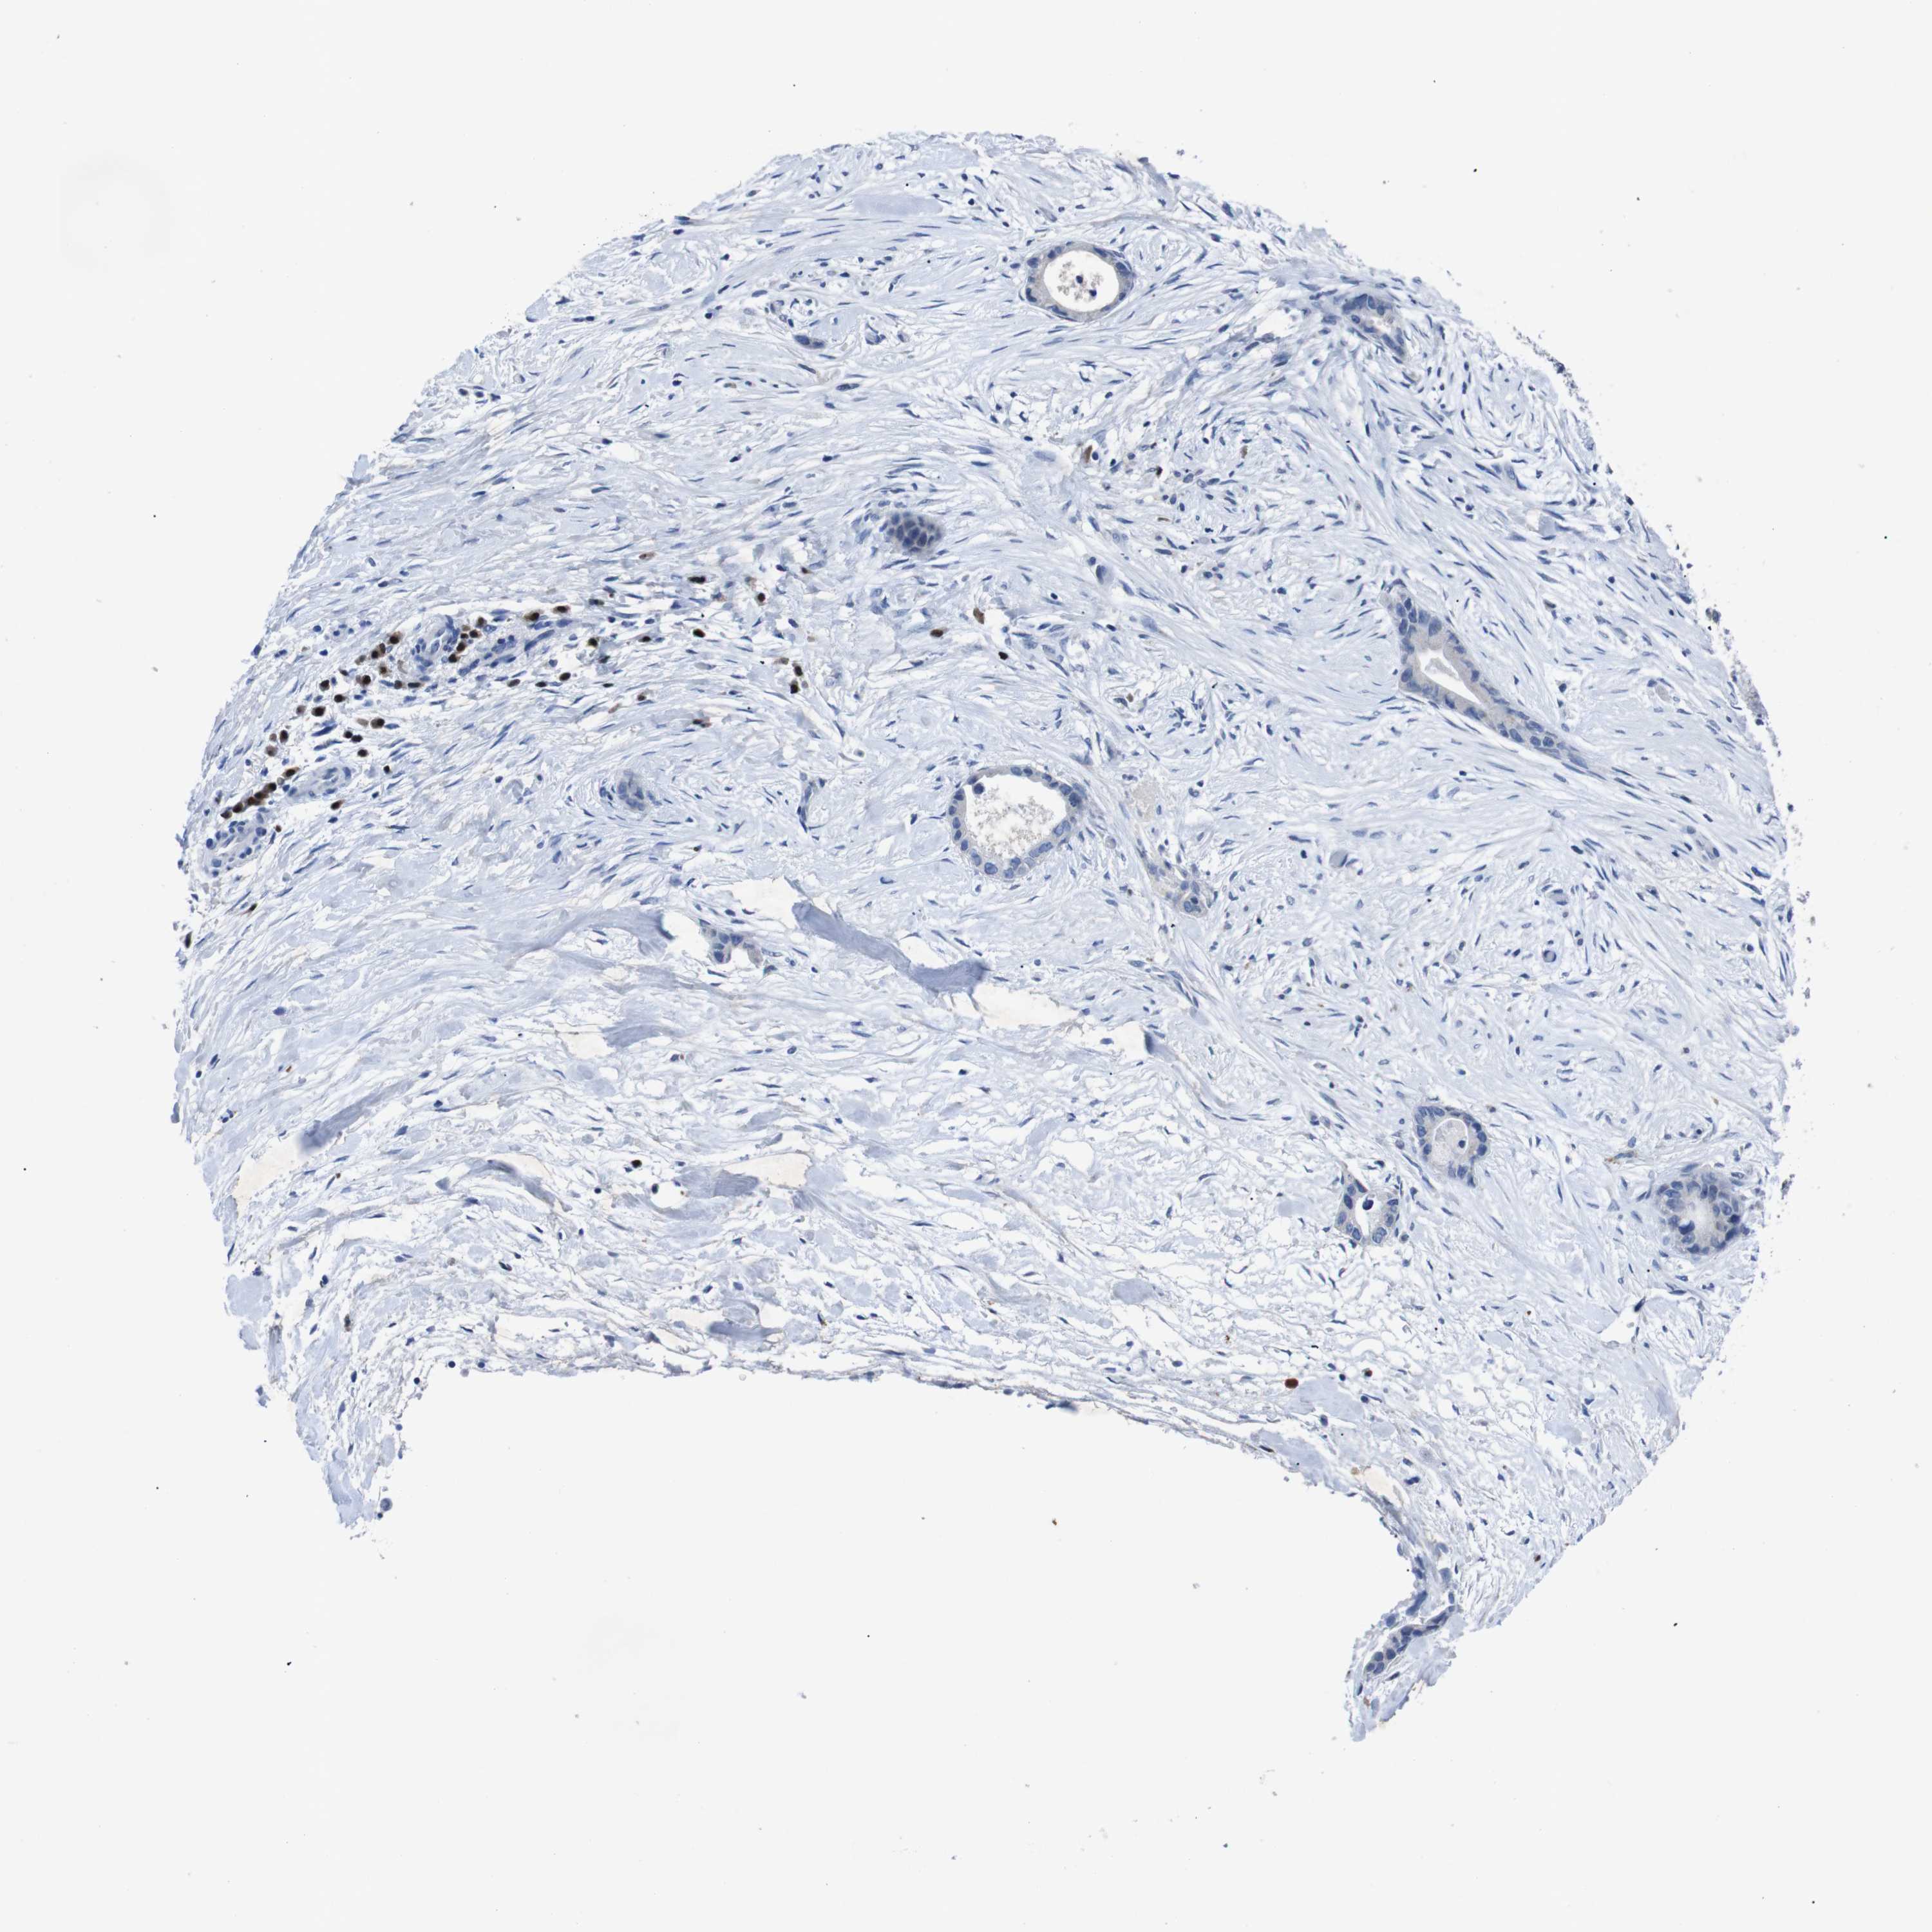

LIVER CANCER - Protein expressioni

A mouse-over function shows sample information and annotation data. Click on an image to view it in a full screen mode. Samples can be filtered based on level of antibody staining by selecting one or several of the following categories: high, medium, low and not detected. The assay and annotation is described here.

Note that samples used for immunohistochemistry by the Human Protein Atlas do not correspond to samples in the TCGA dataset.

Antibody stainingi

Antibody staining in the annotated cell types in the current human tissue is reported as not detected, low, medium, or high, based on conventional immunohistochemistry profiling in selected tissues. This score is based on the combination of the staining intensity and fraction of stained cells.

Each image is clickable and will lead to virtual microscopy that enables deeper exploration of all samples and also displays staining intensity scores, fraction scores and subcellular localization as well as patient and tissue information for each sample.

Antibody HPA002038

Antibody HPA002698

Antibody CAB013508

Staining

High

Medium

Low

Not detected

Intensity

Strong

Moderate

Weak

Negative

Quantity

>75%

75%-25%

<25%

None

Location

Nuclear

Cytoplasmic/membranous

Cytoplasmic/membranous,nuclear

Cholangiocarcinoma

Carcinoma, Hepatocellular, NOS